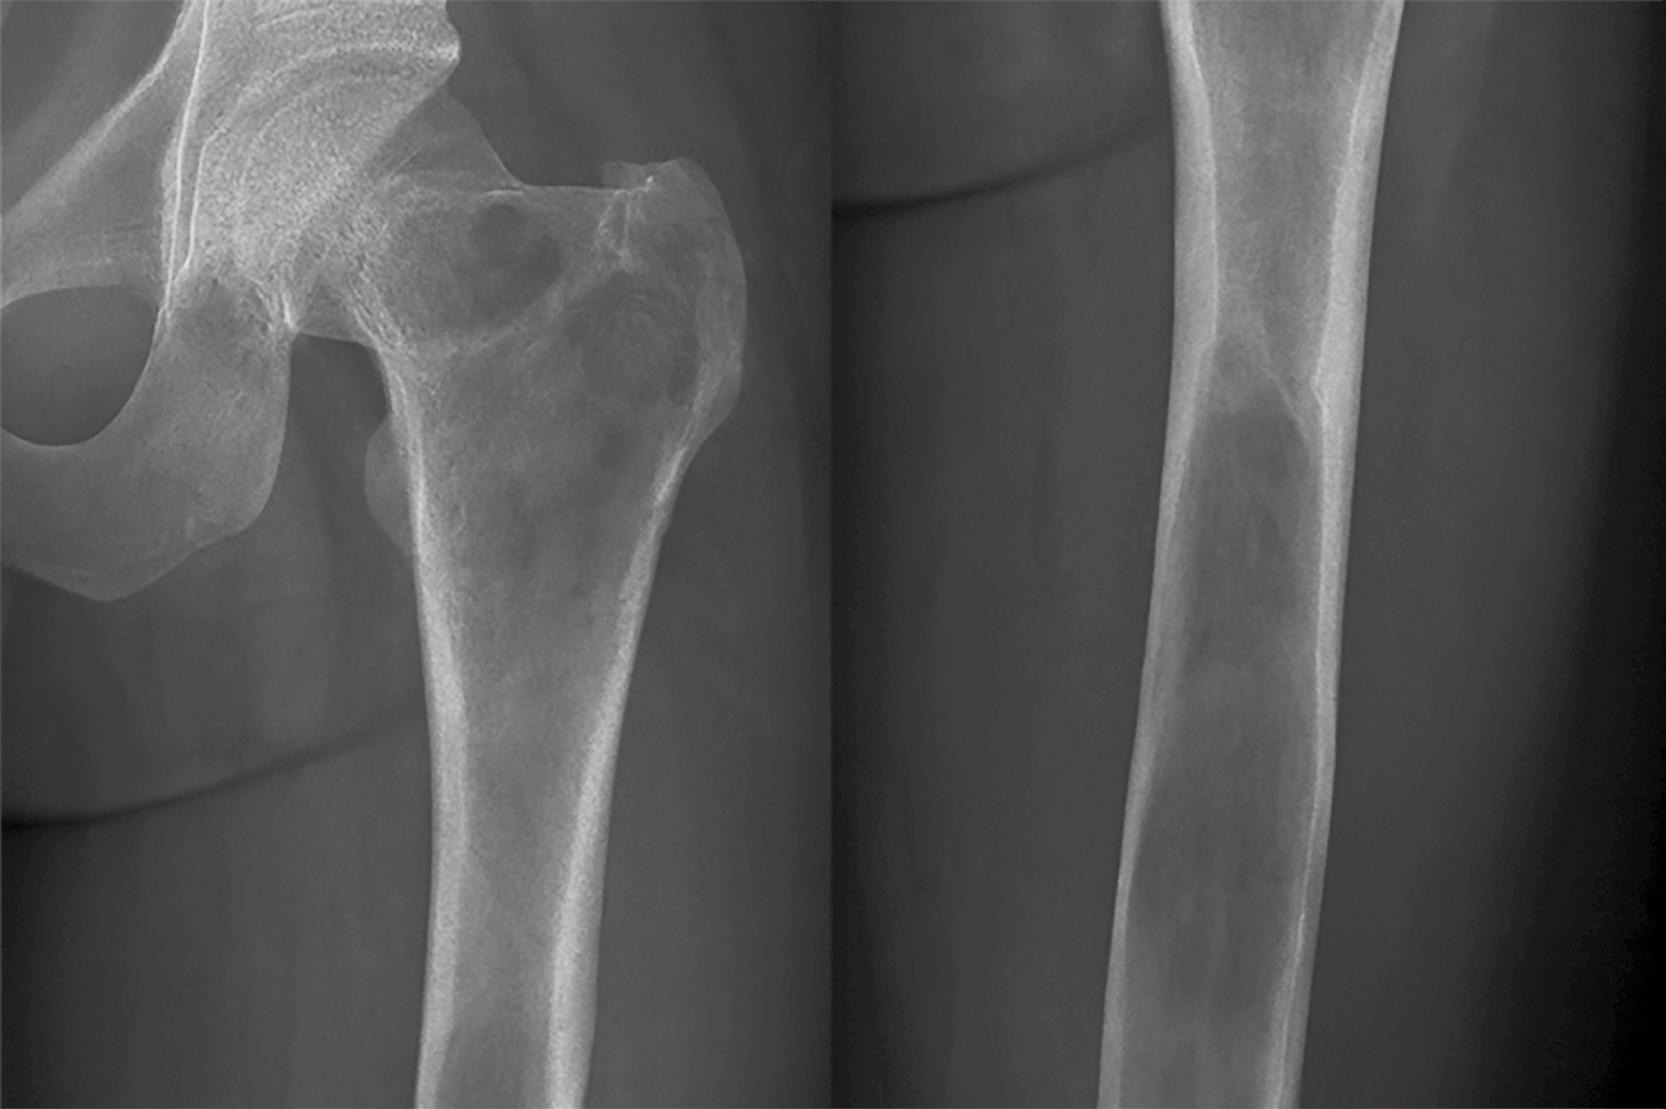

El osteosarcoma es el tumor óseo maligno más común en esta población, seguido por el sarcoma de Ewing, ambos con mayor incidencia entre los 10 y 20 años, lo que coincide con el crecimiento puberal. El osteosarcoma representa entre el 55% al 56% de los tumores óseos malignos en menores de 20 años, con una incidencia global de 3,5 a 8,8 casos por millón al año; predomina en varones y se localiza en las metáfisis de huesos largos como el fémur distal y la tibia proximal. El sarcoma de Ewing, compuesto por células pequeñas y redondas, constituye hasta el 36% de los casos, con mayor frecuencia en adolescentes varones caucásicos, y afecta principalmente el esqueleto axial. En contraste, los tumores óseos benignos, como el osteocondroma o el quiste óseo unicameral, son más comunes en la infancia y suelen diagnosticarse incidentalmente.

Determinar si la lesión se encuentra en la epífisis, metáfisis o diáfisis contribuye a delimitar el espectro de posibilidades diagnósticas. La ubicación anatómica de una lesión ósea dentro del esqueleto puede ofrecer pistas valiosas en el diagnóstico diferencial. Algunos tumores tienen afinidad por ciertas regiones óseas, lo cual, junto con la edad y el patrón radiológico, puede orientar al clínico. Por ejemplo, en zonas como el húmero o alrededor de la rodilla, es común encontrar una amplia variedad de tumores. La Figura 10 y la Tabla 6 agrupan las localizaciones tumorales óseas más frecuentes, lo que permite relacionar patrones de presentación con diagnósticos probables.

Rodilla: todos los tumores, osteosarcoma, sarcoma de Ewing